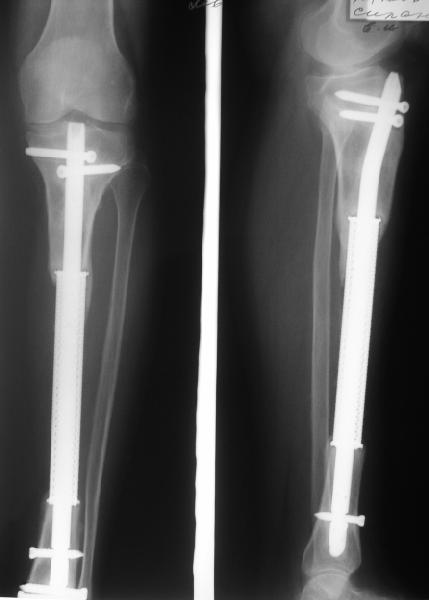

В приложении рентгенограмма через год после операции.